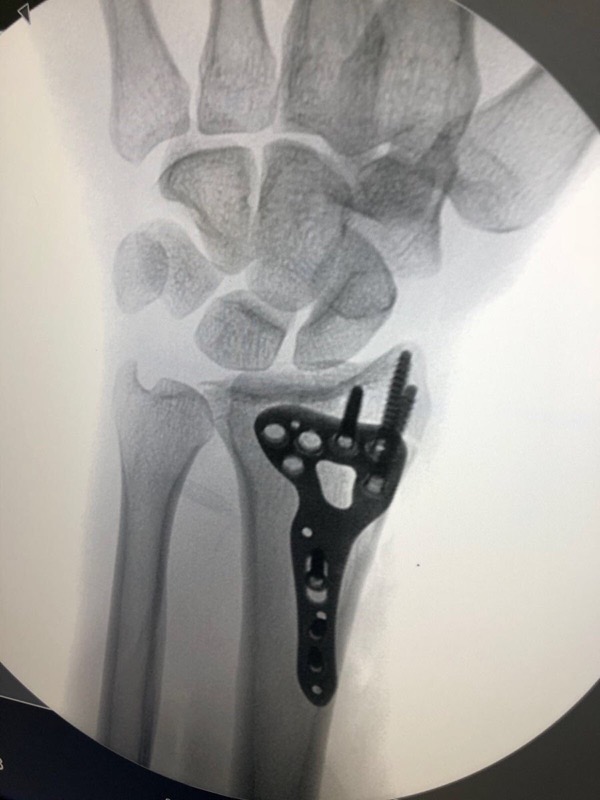

Хорхе Мартин, один из главных претендентов на титул чемпиона мира Moto3 2018 года, словил жесткий хайсайд во время первой практики Гран-При Чехии. Мартин травмировался (перелом левой лучевой кости) и пропустил чешский этап, но он попробует принять участие в Гран-При Австрии. В четверг испанец попробует пройти медицинское обследование, чтобы получить допуск к участию.